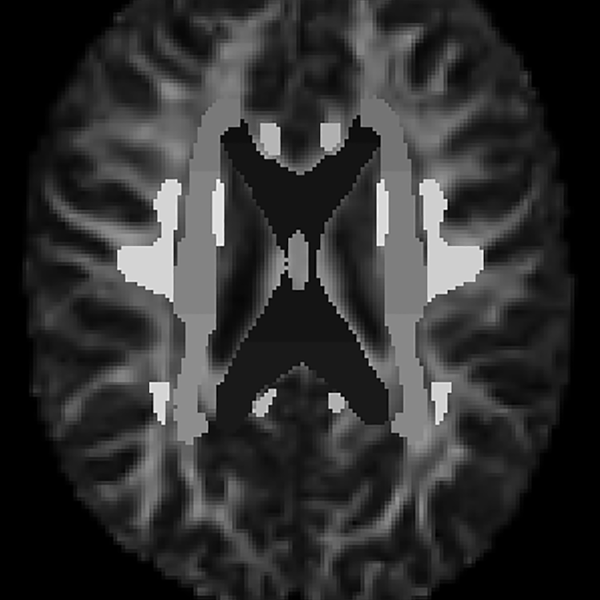

Image credit: Buddha Elemental 3D